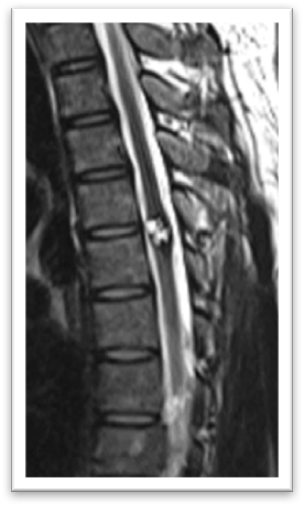

血管母細(xì)胞瘤可發(fā)生于腦組織,脊髓和其他部位,是一種高度血管分化的良性腫瘤。脊髓血管母細(xì)胞瘤在臨床上并不多見,約占所有脊髓占位病的1%-5%。由于脊髓空間較小,腫瘤血運(yùn)豐富,因此此類病變?nèi)绻幚聿缓脤疠^為嚴(yán)重的后果,需要一定的經(jīng)驗和手術(shù)技巧。 脊髓的血管母細(xì)胞瘤常見于胸段,次發(fā)于頸段,隨著腫瘤的生長產(chǎn)生脊髓功能損害的癥狀,如感覺障礙,運(yùn)動功能的喪失,以及大小便的異常。大多生長于髓內(nèi),常和背側(cè)的脊膜關(guān)系密切,常合并較長節(jié)段的脊髓空洞。磁共振對此類疾病的診斷具有重要的意義,表現(xiàn)為邊界清楚的實性病變,有明顯的增強(qiáng),常合并脊髓空洞的表現(xiàn)。一經(jīng)診斷手術(shù)治療 是首選。這類腫瘤在術(shù)中應(yīng)該嚴(yán)格沿腫瘤邊界分離,注意保護(hù)脊髓組織,必要時可行術(shù)中熒光造影確定腫瘤的供血血管。此類腫瘤為良性腫瘤,經(jīng)過恰當(dāng)?shù)闹委熆梢匀〉幂^好的預(yù)后。 近期病例: 51歲男患 以雙下肢無力多年,加重3個月為主訴入院。MRI提示胸3水平髓內(nèi)占位病病變。術(shù)中見腫瘤紅色,血管豐富,位于髓內(nèi)。分離腫瘤和脊髓邊界,全切腫瘤,未輸血。術(shù)后患者下肢肌力明顯好轉(zhuǎn),現(xiàn)隨訪中。 術(shù)后病理回報: 血管母細(xì)胞瘤